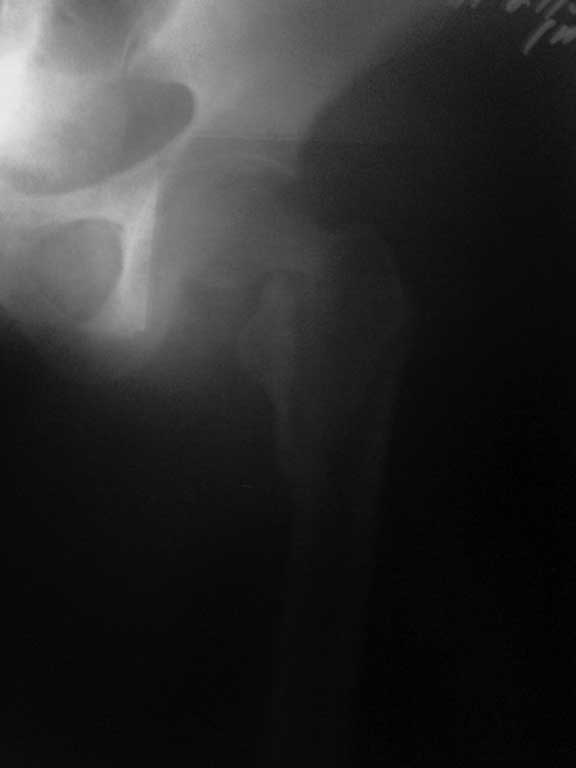

перелом шейки бедра

Уважаемые коллеги!! К нам поступила женщина 41го года, кататравма-

вышла с 4го этажа в состоянии алкогольного опьянения. В итоге чрезвертельный перелом, перелом шейки бедра, импрессионный перелом головки бедра. Прошу прощения за снимкм- выложу в субботу покачественнее. В отделении пока думали что делать выдала алкогольный психоз. В итоге- мысли такие- остеосинтез пластиной с винтами АО в шейку или DXS - это то что есть в больнице. Гамму не купит- никого нет и никому она не нужна. Смущает то что шейка очень узкая и винт DXS ее может развалить- тогда пластина и винты АО. КТ пока возможности сделать нет. Что посоветуете?? Огромное спасибо.